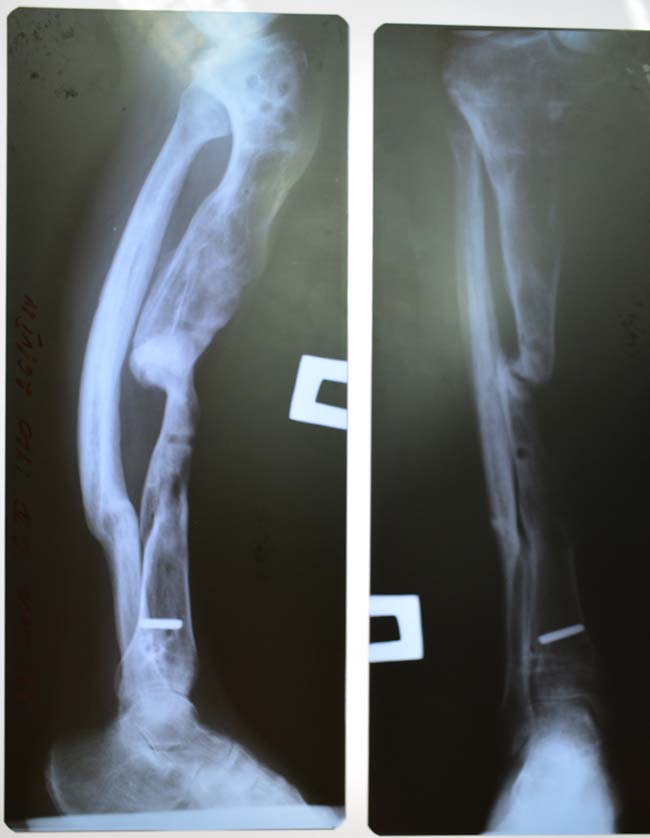

- рентген — застосовується як базове обстеження, особливо для оцінки змін кістки.